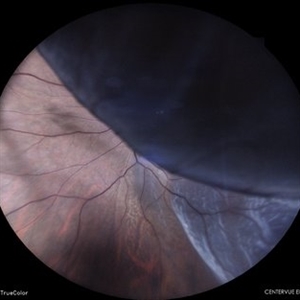

Giant Retinal Tear with Retina Detachment, Both Eyes

Fundus photograph of a 13 year-old female with giant retinal tear and retinal detachment in both eyes.

Photographer: Dr. Akansha Sharma-Retina Foundation, Ahmedabad

Condition/keywords: giant retinal tear, proliferative vitreoretinopathy (PVR)